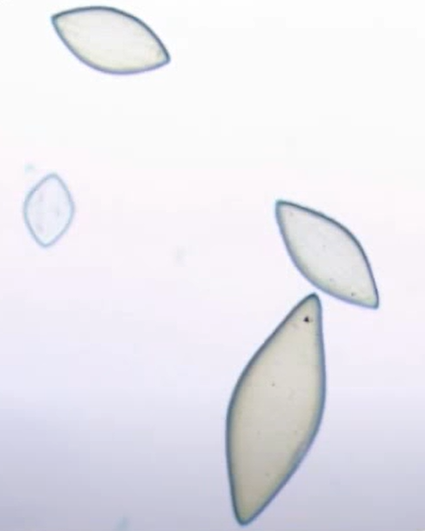

Cristais de oxalato de cálcio mono-hidratado

Cristais de oxalato de cálcio di-hidratado

Cristal de oxalato de cálcio di-hidratado